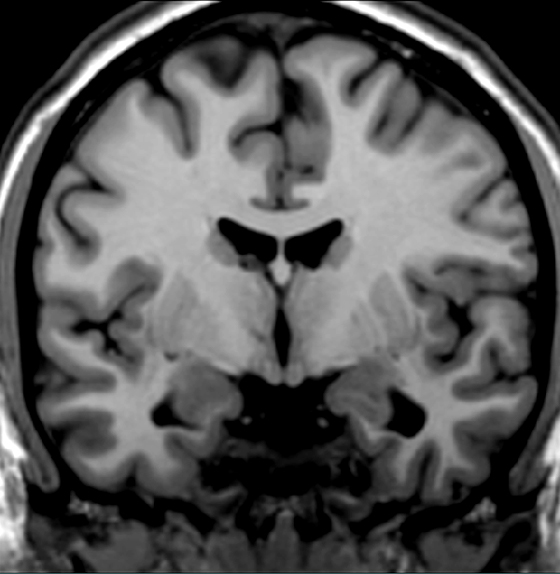

It is proposed that excessive activity of this structure contributes to the bradykinesia, rigidity and tremor seen in patients with Parkinson's disease. Locate the structure in this scan.